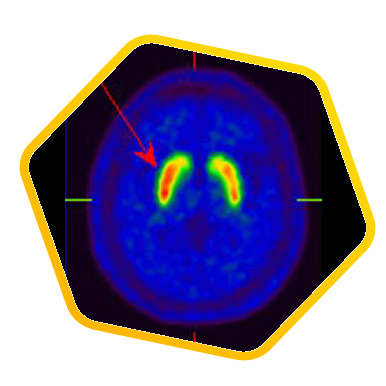

Neurology

![]() [C-11] PIB |

![]() [C-11] Raclopride |

![]() [F-18] DOPA |

PET/CT scans with special tracers can show 3-dimensional images of blood flow and biomolecules deposition in the brain for diagnosis and monitoring the therapy progress of various neurological diseases, such as Alzheimer's, Dementia, Parkinson's disease, Huntingdon's chorea and autism. In 2018, the National Institute on Aging-Alzheimer's Association (NIA-AA) had revised the definition of Alzheimer's Disease (AD) from a syndrome diagnosed by a set of clinical criteria to a biological construct using abnormal protein deposits to define AD as a unique neurodegenerative disease that can lead to dementia. Our hospital has almost 20 years of experience in producing specific tracer to detect abnormal protein deposition in the brain.

- Epilepsy

For some types of epilepsy patients, PET/CT scans can localize the epilepsy-causing focus in the brain. Modern stereotaxic neurosurgery can then cure epilepsy permanently by excising the focus.